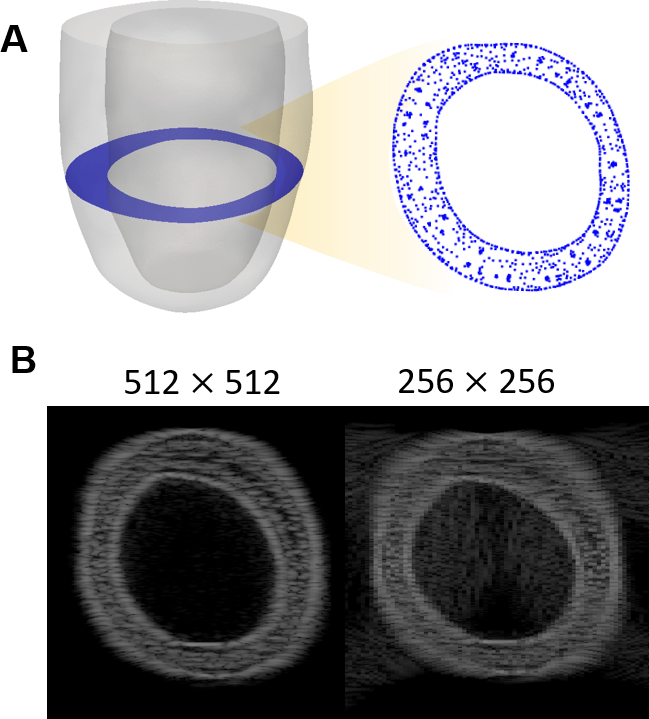

where c is the wave speed, f is the wave number, ϕitalic-ϕ\phiitalic_ϕ is the phase, and A and B are the wave amplitudes in the x and y directions, respectively. The response amplitude was determined to be a normal distribution, with apodization performed using the built-in functions of Field II, and the resulting voltage trace was converted to 8-bit images of a fixed resolution of 512 ×\times× 512 pixels. Furthermore, the images were downsampled to predefined sizes of 128 ×\times× 128 and 256 ×\times× 256 to perform different standards of motion calculations. Here, the 512×512512512512\times 512512 × 512 image corresponds to a resolution of 1 px/mm, whereas the 256×256256256256\times 256256 × 256 describes 0.5 px/mm. Given the rapidness of the wall motion and the fineness of the mesh describing the geometry, the synthetic images presented different sources of artifacts. The images created from the FE simulations were presented at the mid-slice of the mouse-specific geometry for three sets of spatial resolution (Fig. 2A).

Refer to caption

Figure 2: (A) Mouse-specific left ventricle geometry, with the midsection highlighted in blue. (B) Synthetic ultrasound images were created through rasterization of the finite element simulations of the geometry during a cardiac cycle followed by a method simulating standard B-mode phased linear array imaging. The images were generated through scanning, scattering, and apodization by adopting an acoustic wave impulse response. The original image of (left) 512 ×\times× 512 pixels was also downsampled to (right) 256 ×\times× 256 pixels.